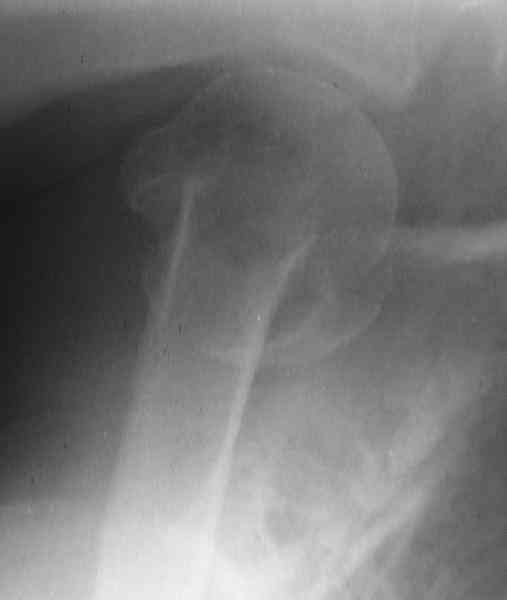

Hello,I am presenting a case of 80 year old male patient right handed known case of hypertension, diabetes and history of CVA 2 years back had a fall in the hosue 10 days back and came to me for pain and ecchymosis around the right shoulder. Xray shows evidence of comminuted fracture proximal humerus extraarticular. He is a doctors father and the doctor wants to know is there any minimally invasive procedure we can do ... I have advised him to go for complete surgery in the form of the AO locking plate under general anesthesia. He is a little reluctant for complete general anaesthesia. My questions to the house is ...1. Is there any other option besides the locking plate ?? (Less invasive) 2. If he is not medically fit for surgery, then can we leave him alone if yes what are the chances of going it into non union? Awaiting your reply Dr Neeraj Bijlani

Fragments now look severely displaced.